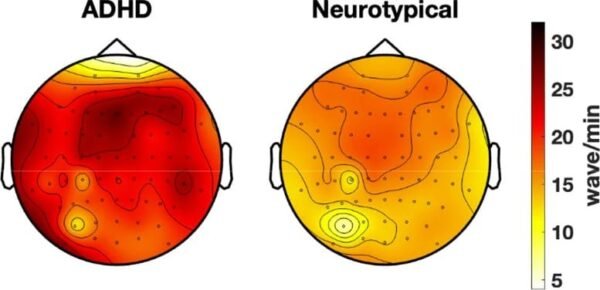

Mokslininkai atrado, kad SDDH turinčių žmonių smegenys generuoja miego bangas budrumo metu, kas gali paaiškinti dėmesio sutrikimus.